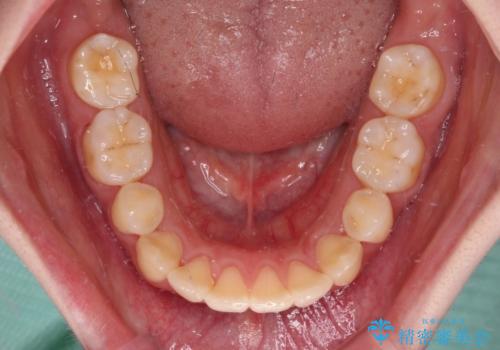

- 高校生の時に矯正治療を行ったものの、後取りをしてしまったとのことで来院された患者様です。

マウスピースでもワイヤー矯正でも対応可能でしたが、再度ワイヤーは装着したくないとのことでインビザラインにて矯正治療を行うこととしました。

舌の突出癖が原因で後戻りをしたため、舌のトレーニングをしっかりと行っていただき、口元の突出感を改善することができました。